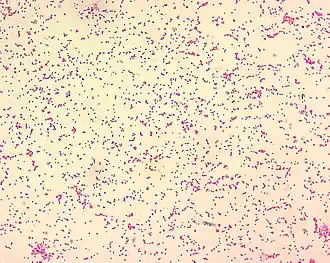

Патогенными для человека являются три представителя рода бруцелл: возбудитель бруцеллёза мелкого рогатого скота (Brucella melitensis), возбудитель бруцеллёза крупного рогатого скота (Brucella abortus) и возбудитель бруцеллёза свиней (Brucella suis)[4]. Есть описанные случаи заболевания бруцеллезом после контакта с штаммами Brucella canis.(эти случаи считаются редкими).[5] Бруцеллы очень мелкие, неподвижные, не образуют спор, но при определённых условиях могут образовывать капсулу. Характерен полиморфизм микробных клеток — в одном препарате можно встретить кокковые, овоидные и палочковидные формы. Они легко окрашиваются всеми анилиновыми красителями, грамотрицательны[6].